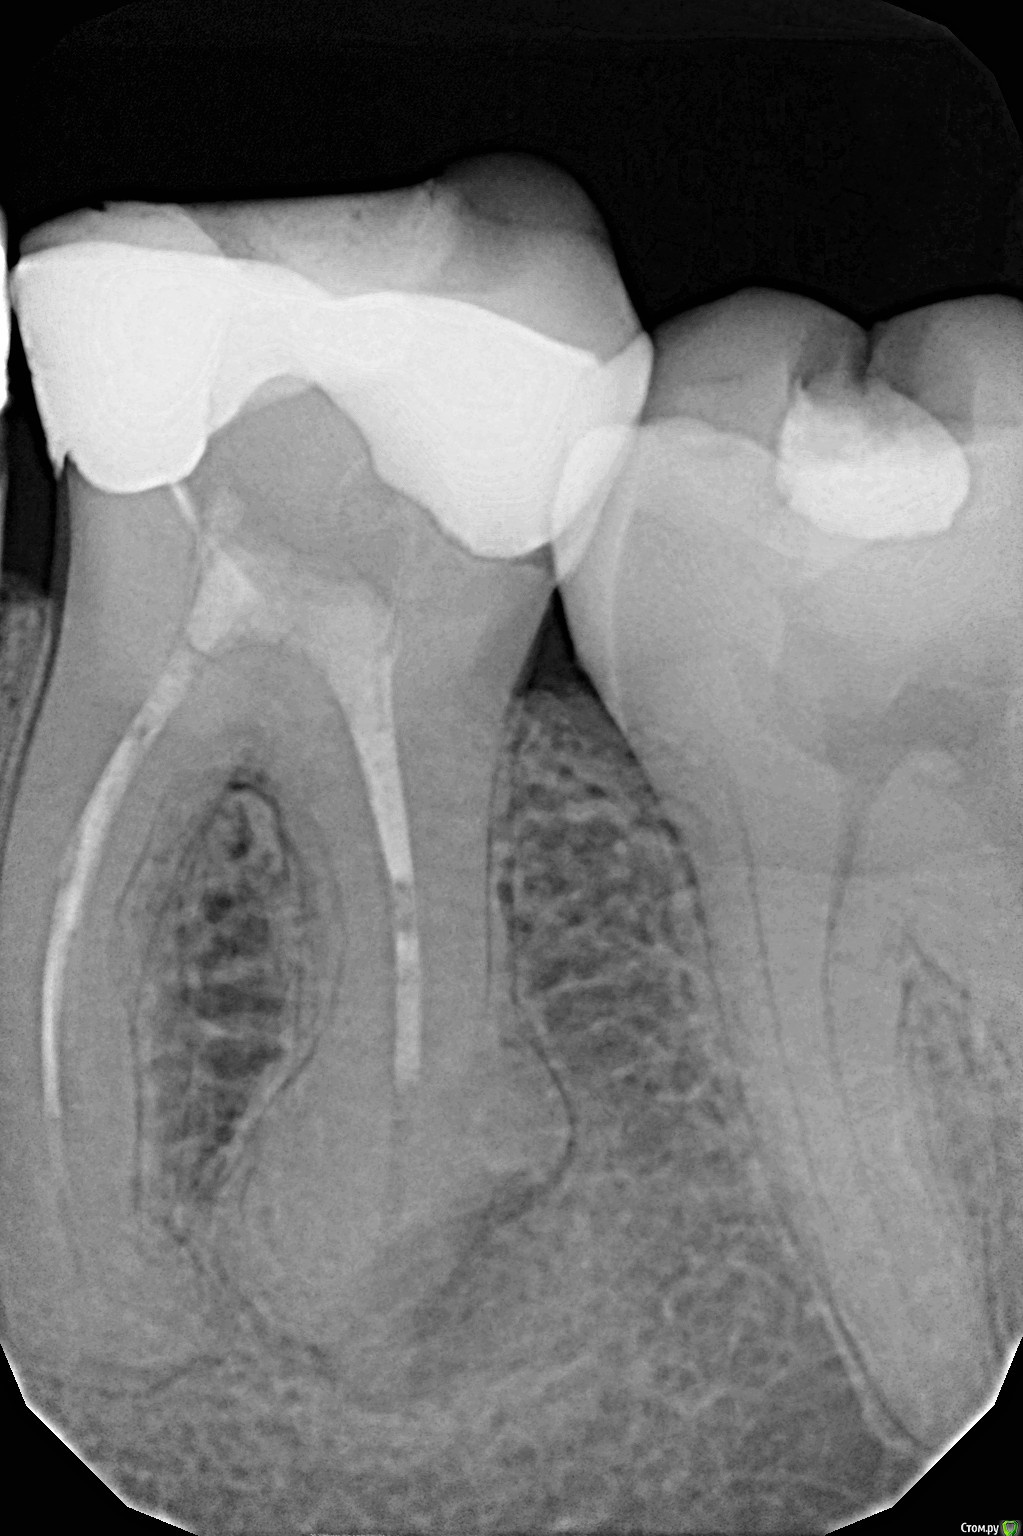

Здравствуйте! Нашли кисты/ гранулемы в зубах - 24

Подскажите , пожалуйста, есть ли там действительно воспаления , которые нужно лечить (нижний- понятно, что надо, сомнения насчет верхнего).

ПС прицельный снимок есть только нижнего зуба